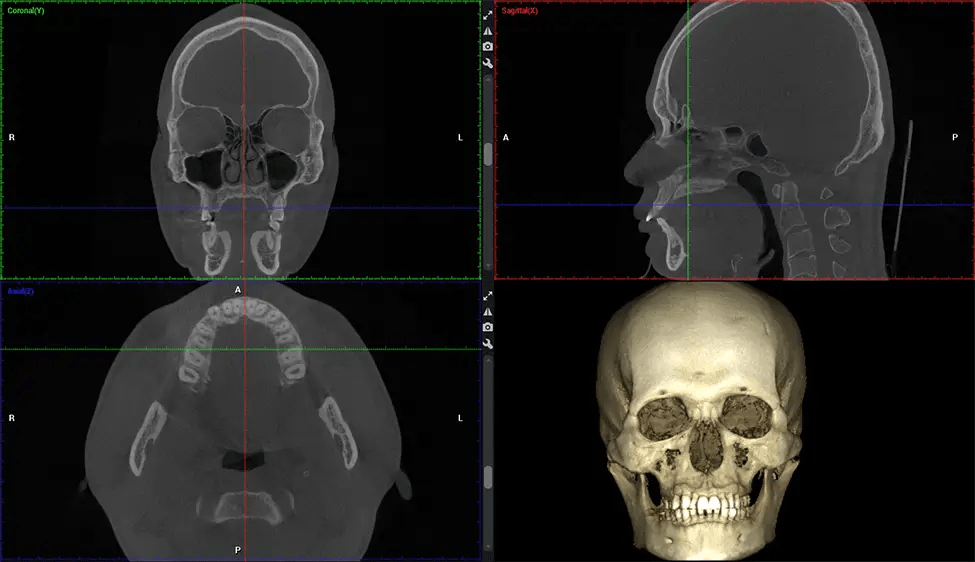

Cone Beam Computed Tomography (CBCT) is an advanced imaging technique used in dentistry and maxillofacial surgery to obtain detailed 3D images of the oral and maxillofacial structures. At Dr G Dental Studio, our CBCT scanners utilize a cone-shaped X-ray beam and a specialized detector to capture images from different angles. A computer then combines these images to create a 3D representation of the patient’s oral anatomy.

This 3D scan, called cone beam computed tomography, gives your dentist a more complete image of your oral anatomy and disease processes than a traditional X-ray. Unlike conventional X-rays, which capture a 2D image of your mouth from various angles, a 3D scan takes multiple digital X-rays for one image. It provides a complete view of your jaw, teeth, nerves, and soft tissues. This enhanced view allows dentists to detect minor issues not visible in traditional 2D scans, such as impacted wisdom teeth or bone fractures in the sinus cavity.

There are many benefits to using CBCT technology, especially compared to the traditional 2D X-ray format. One of the most significant advantages of CBCT scans is that they provide much more information than traditional X-rays. A scan lets your dentist see images from all angles of your jaw and mouth, including your sinuses, nasal cavity, cheekbones, and other surrounding areas. This added information helps your dentist craft a comprehensive treatment plan that addresses all aspects of your oral health.

After the scanning process, the captured X-ray images are processed by the CBCT software, which applies algorithms to reconstruct a detailed 3D image of the scanned area. The software compiles these individual X-ray images and creates a digital 3D representation of the patient’s anatomy. The reconstructed 3D CBCT image can be viewed and analyzed by the dentist or radiologist. This image can be manipulated, rotated, and zoomed in or out to examine specific structures and evaluate the patient’s condition.

Planmeca Viso G7 CBCT ( Cone Beam CT Scan ) is designed to surpass the demands of industry leaders, specialists, and large institutions. It’s has a large ø25×30 cm sensor with four built-in cameras. It can capture unlimited volume sizes from a ø3×3 cm to a ø30x30cm volume capturing the skullcap through C7 on the cervical spine. The Planmeca Viso G7 offers the industry’s largest single volume scan of ø30×19 cm. It’s poised to handle advanced imaging modalities such as Planmeca ProFace® and Planmeca 4D™ Jaw Motion technology. The occipital head support allows an unimpeded view of facial tissue.